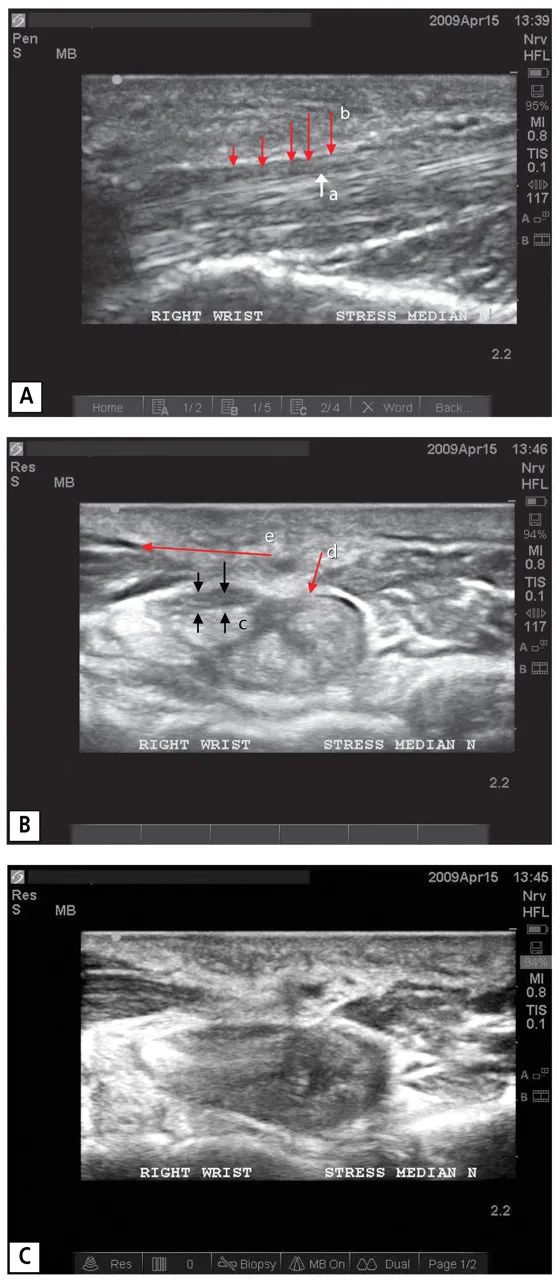

然后對正中神經(jīng)進行縱向和橫向成像,在中立位放松的位置,對正中神經(jīng)隧道進行橫向成像。在動態(tài)壓力測試(DST)期間重復成像,動態(tài)壓力測試包括用硬橡膠球做阻力,讓拇指尖對食指和中指指尖進行持續(xù)的等長收縮(圖2)??v向成像(圖3A)和橫向成像(圖3B)在中立、預應力位置顯示正常。然而,在動態(tài)壓力測試期間,縱向成像顯示正中神經(jīng)明顯變平,有一段神經(jīng)被壓迫在腕管中部(圖4A)。在橫斷面上也有類似的發(fā)現(xiàn),動態(tài)壓力測試期間正中神經(jīng)伸長和變平(圖4B-4C)。

這些發(fā)現(xiàn)表明,當腕部肌肉群收縮并收緊腕橫韌帶時,肌肉的一部分向腕管內背側凸出(圖4B-4C)。同時,收縮的屈肌,讓腕管變得更硬,增加了壓迫效果——正中神經(jīng)被 "夾在 "腕橫韌帶和屈肌腱之間。

圖四

一名患有腕管綜合征的24歲男子的右手腕的應力超聲圖像(病例1)。在縱向圖像(A)中,向上的小箭頭(a)表示正中神經(jīng)受壓的區(qū)域,可見白色箭頭左側和向下的紅色箭頭(b)下方沿正中神經(jīng)的凹陷或變平。在橫向圖像(B)中,正中神經(jīng)被拉長和壓扁(箭頭c),因為腕橫韌帶向背側凸出(箭頭d)。腕部肌肉群(左邊的深色楔形區(qū)域)收縮并將韌帶拉向左邊(箭頭e),使正中神經(jīng)正上方的韌帶部分變平。

在最大壓力的橫向圖像(C)中,患者增加拇指和手指屈曲收縮的強度,可以看到正中神經(jīng)變得更平??梢钥吹酵蟛考∪夂屯髾M韌帶的邊緣進一步侵入腕管,抵住正中神經(jīng)。